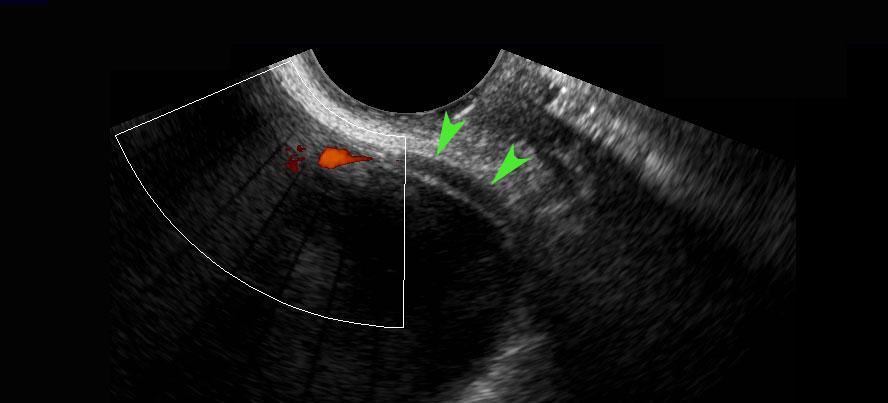

Ở người phụ nữ này, đoạn niệu quản xa bình thường (đầu mũi tên) đã được hiển thị, bao gồm cả “hiện tượng tia phụt” của niệu quản khi sử dụng Doppler. Lưu ý khoảng cách nhỏ giữa đầu dò âm đạo và niệu quản đoạn xa.